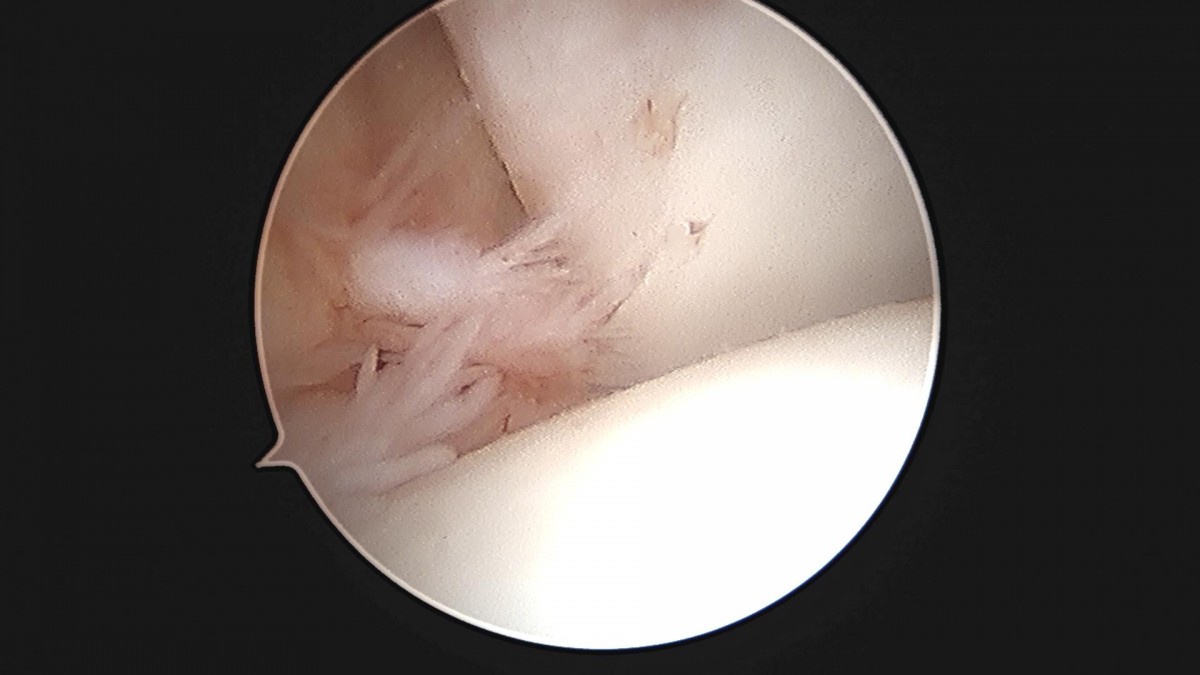

이재상 원장님 발목 인대봉합술 및 활막 절제술 조한O 환자

d4279b3b94d98ed627b1644855bcf9f2_1699600790_1381.jpg

d4279b3b94d98ed627b1644855bcf9f2_1699600790_4678.jpg

d4279b3b94d98ed627b1644855bcf9f2_1699600790_7868.jpg

d4279b3b94d98ed627b1644855bcf9f2_1699600791_1412.jpg

d4279b3b94d98ed627b1644855bcf9f2_1699600791_4843.jpg

d4279b3b94d98ed627b1644855bcf9f2_1699600791_8349.jpg

d4279b3b94d98ed627b1644855bcf9f2_1699600792_1815.jpg

d4279b3b94d98ed627b1644855bcf9f2_1699600792_5333.jpg

d4279b3b94d98ed627b1644855bcf9f2_1699600792_8773.jpg